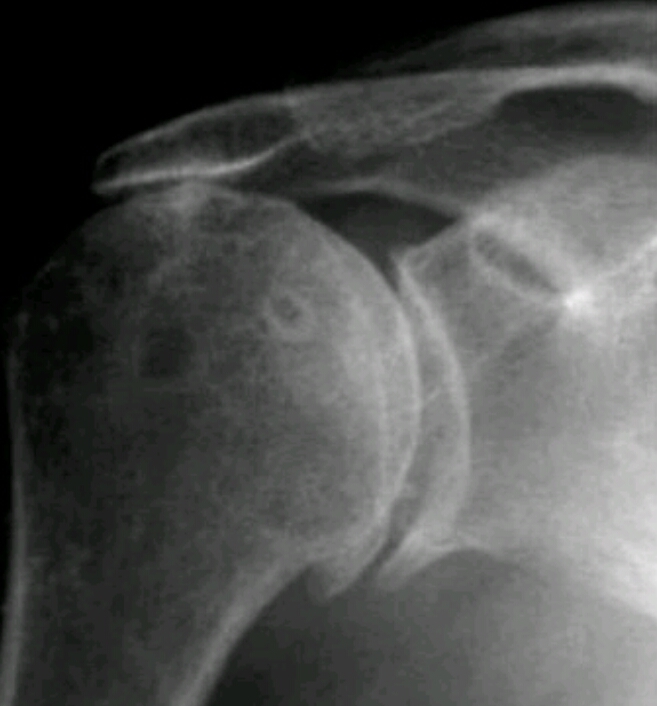

What disease is this? What features make the diagnosis?

Rotator cuff arthropathy

cystic changes

superior migration of humerus due to unopposed deltoid

erosions at acromion